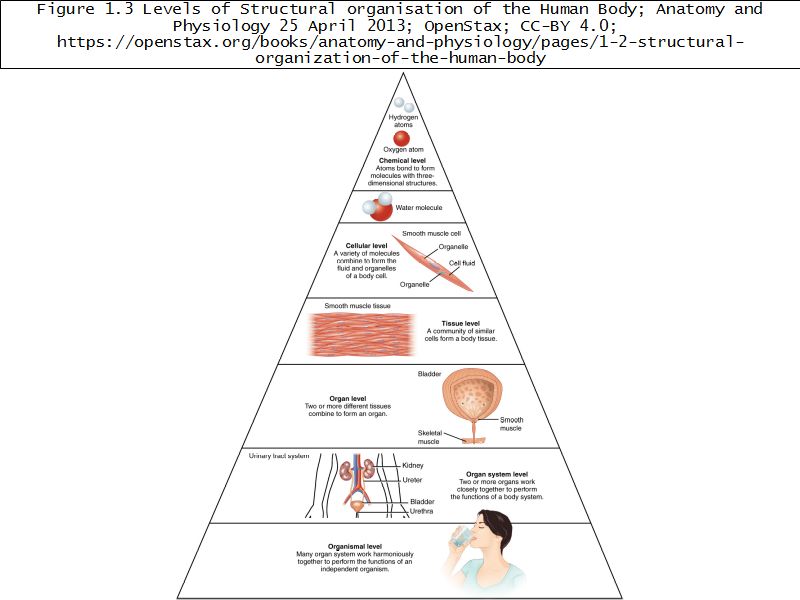

Levels of Organisation

Why histology?

- Knowledge

- Because all knowledge is worthwhile

- The more you know, the more you are able to know

- Know the normal to identify the abnormal

- Pathology

- Functions of many organs

- Lung, Kidney, Liver

- Informed by cellular organisation

- Physiology

- Structure of body informed by cellular organisation

- Anatomy

- Inflammation, Repair & Treatment dependent on cellular organisation

- Pharmacology